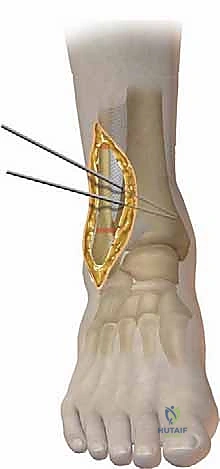

| قطع العظم الإسفيني المفتوح (Opening Wedge Osteotomy) | يتم عمل شق في العظم وفتحه لإضافة زاوية، ثم يُملأ الفراغ بطعم عظمي (Bone Graft) صناعي أو من المريض. | يطيل العظم (مفيد إذا كان هناك قصر في الساق)، دقيق جداً في التصحيح. | يحتاج إلى طعم عظمي، قد يستغرق وقتاً أطول للالتئام. |

| قطع العظم الإسفيني المغلق (Closing Wedge Osteotomy) | يتم إزالة مثلث (إسفين) صغير من العظم، ثم تُغلق الحواف على بعضها لتصحيح الزاوية. | التئام أسرع (عظم مقابل عظم مباشرة)، لا يحتاج لطعم عظمي. | يؤدي إلى قصر طفيف جداً في طول الساق، لا ينصح به للمرضى الذين يعانون من قصر الساق أصلاً. |

- قص العظم (Osteotomy): باستخدام منشار جراحي دقيق وموجهات خاصة، يتم قص عظم الظنبوب (وفي بعض الأحيان عظم الشظية أيضاً) بالزاوية التي تم تحديدها مسبقاً في التخطيط الثلاثي الأبعاد.

- التثبيت الداخلي (Internal Fixation): بمجرد الوصول للزاوية المثالية، يتم تثبيت العظم في وضعه الجديد بقوة باستخدام شرائح معدنية متطورة (Locking Plates) ومسامير من التيتانيوم. هذا التثبيت القوي يضمن عدم تحرك العظم أثناء فترة الالتئام.